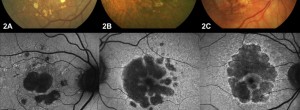

Geographic atrophy phenotype identification by cluster analysis

Drusen Ooze: A Novel Hypothesis in Geographic Atrophy